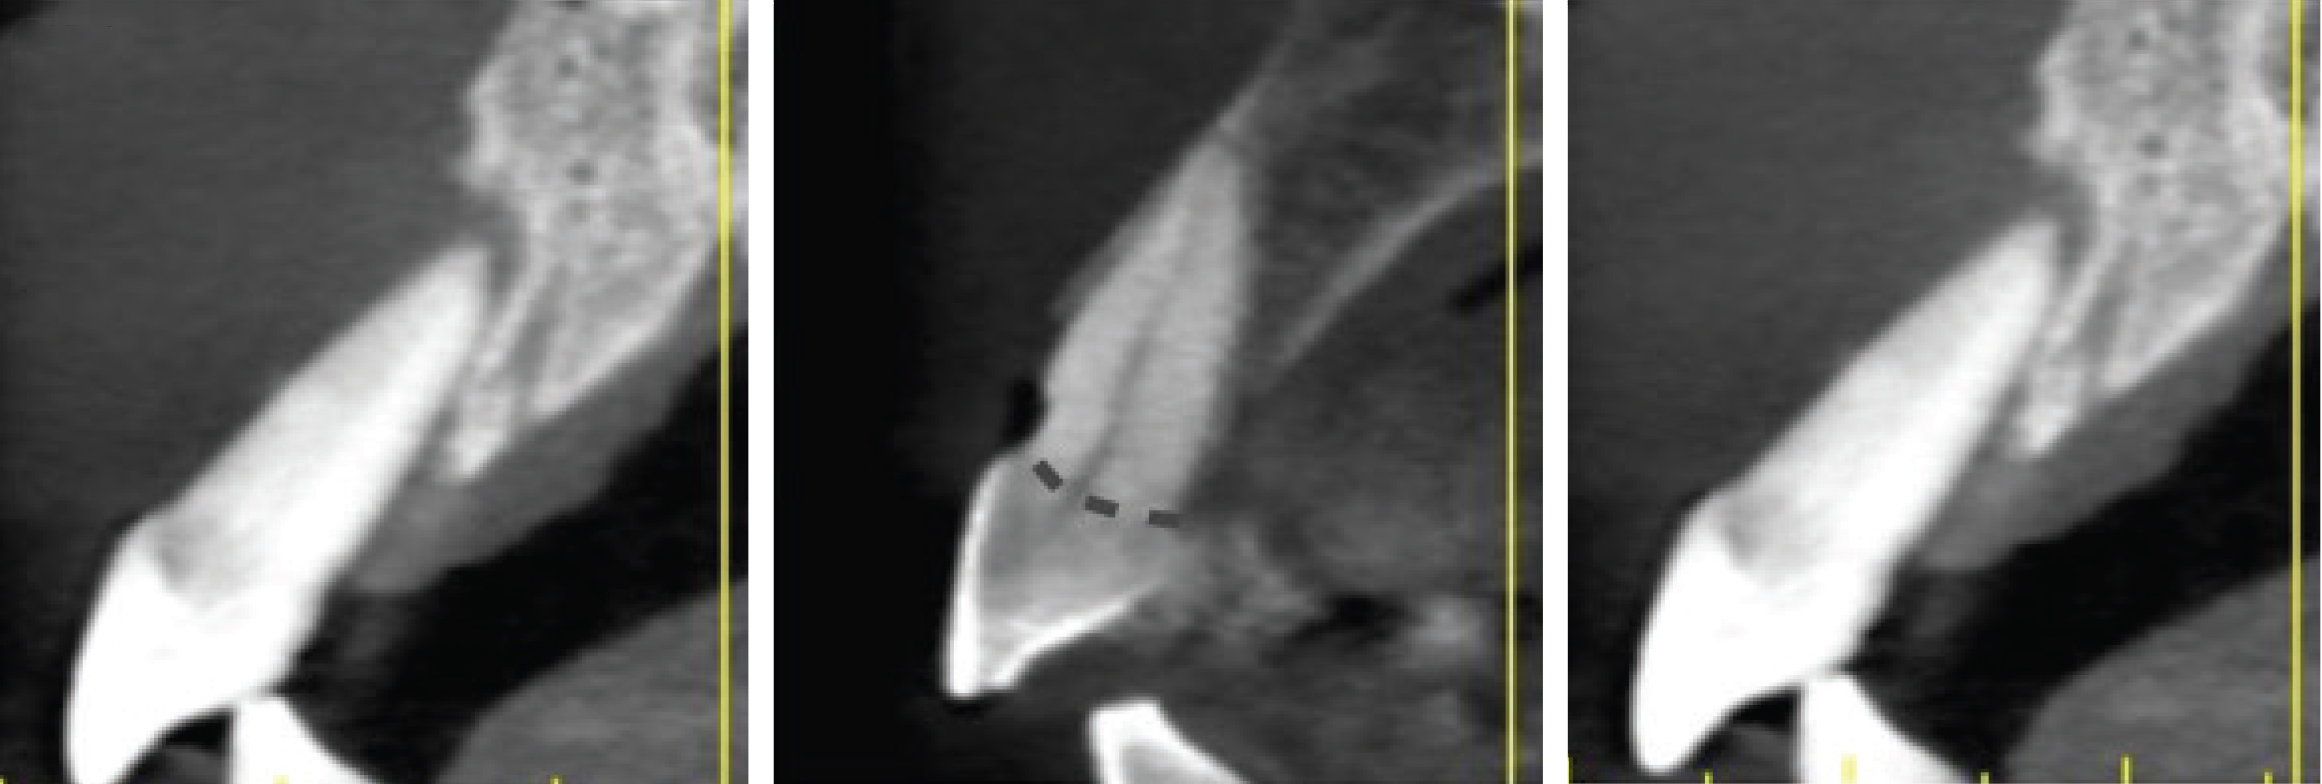

Sagittal cross-sections of CBCT images depicting Grade I (Left), Grade II (Center), and Grade III (Right) sockets. Note the level of the buc- cal plate relative to the cementoenamel junction that is elucidated by this cross-cut.

Grade I sockets are the most ideal. Following tooth extraction, a socket that has an intact buccal plate, adequate interproximal bone, and satisfactory apical topography will fall into this category. In this classification, an intact buccal plate is defined as having no fissures or dehiscences and less than 25% loss of height (Figure 4, left; Figure 5, left). This percentage of buccal plate loss was selected as the cutoff based on the average root length of single-rooted teeth, which is 14.2 mm,25 and the amount of buccal plate that can be reliably regenerated during immediate implant placement. Adequate apical topography is defined as enough bone present apical to the extraction site to allow for engagement of 3 mm to 4 mm of a properly positioned immediate dental implant (Figure 2).1,2 Adequate interproximal bone is defined as no or mild (up to 2 mm) periodontal bone loss on the adjacent teeth as to allow for support of the interproximal soft tissue and to enable placement of the platform of an immediate implant in the proper apical-coronal position relative to the adjacent teeth while still being bordered by bony walls on the mesial and distal aspects26 (Figure 3, left).

Grade II sockets are differentiated from Grade I by the amount and quality of the remaining buccal plate. A Grade II socket has a fissure, dehiscence, or deficiency of the buccal plate totaling a 25% to 50% loss. Like Grade I sockets, they have adequate interproximal bone and apical topography (Figure 3, left; Figure 4, center; Figure 5, center).

Grade III sockets are the most deficient and include any socket with inadequate apical topography, insufficient interproximal bone, or more than 50% loss of buccal plate. Inadequate apical topography is defined as not enough bone present apical to the extraction site to allow for implant placement and may be the result of bone loss caused by periapical lesions or concavities due to existing anatomy of the alveolus (Figure 4, right; Figure 5, right). Insufficient interproximal bone is defined as moderate-to-severe periodontal bone loss—greater than 2 mm on one or both of the adjacent teeth.